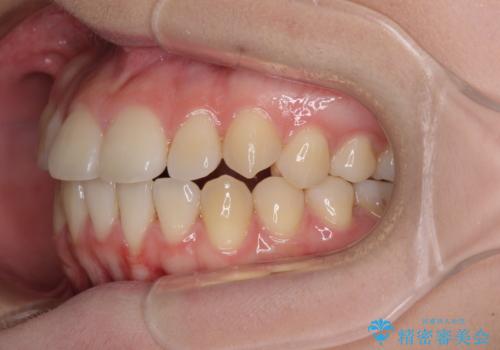

カリエール・ディスタライザーとインビザラインを用いた八重歯の改善

- 前歯の叢生と上顎左右の八重歯を気にして来院された患者様です。

奥歯の咬み合わせを見ると、左側は上顎が下顎に対して相対的に前方にあり、上下の前歯が接触していない状態でした。

咬み合わせを改善するためには、左側上顎臼歯を後方に移動させた咬み合わせにする必要があります。

インビザライン単体で改善することも可能性もありますが、インビザライン単体で達成する可能性が低いと考えられたため、カリエール・ディスタライザーという補助装置を併用して、より確実性を上げることとしました。

奥歯の咬み合わせを改善しながら、並行してインビザラインで歯列を整えることとしました。

カリエールディスタライザーを併用したことで、左側臼歯の咬み合わせを確実に改善させることができました。